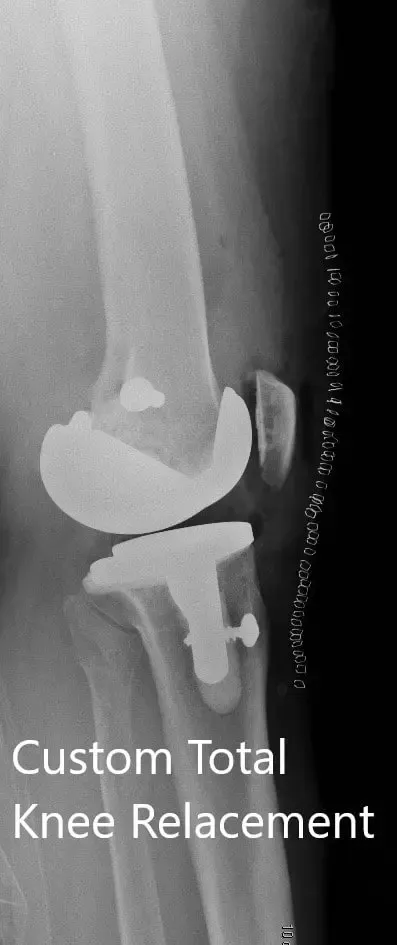

Imágenes postoperatorias que muestran vistas AP y laterales de la rodilla derecha